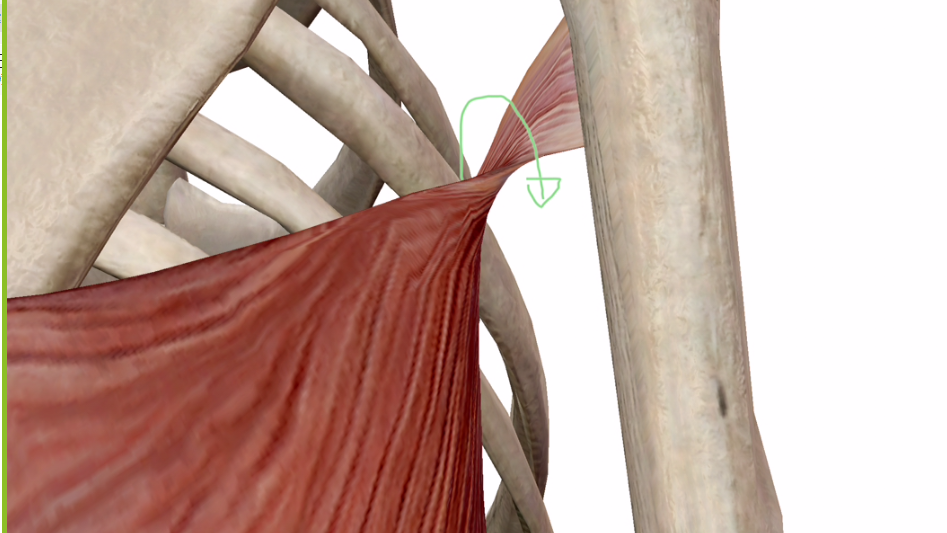

この、腕に付く部分のねじれです。

別角度はこちら↓

ねじれてますね。

これ、なんでねじれているのでしょう?

このねじれについてもどこの文献を探しても答えは見つかっていませんが、ひとつの仮説は立っています。

このねじれの方向からすると、腕を前に出したときにねじれが解消します。

もしかしたら、人間がおさるさんで4足歩行の時に腕を常に前に出して歩いてたので、その名残なのではないだろうかと考えています。